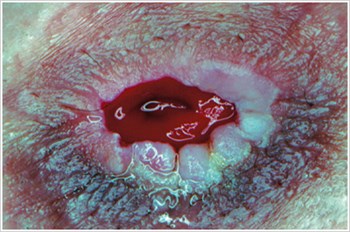

Pyoderma Gangrenosum

Popis/príčiny:

Zápalové ochorenie kože často pozorované u pacientov so zápalovým ochorením čriev ( IBD ), ako je Crohnova choroba alebo ulcerózna kolitída.

Symptómy:

- Nepravidelne tvarované, červené, bolestivé, infikované vredy, s červenými až fialovými valcovanými okrajmi; sa objavujú na nohách, zadku, tvári a peristomálnej oblasti.